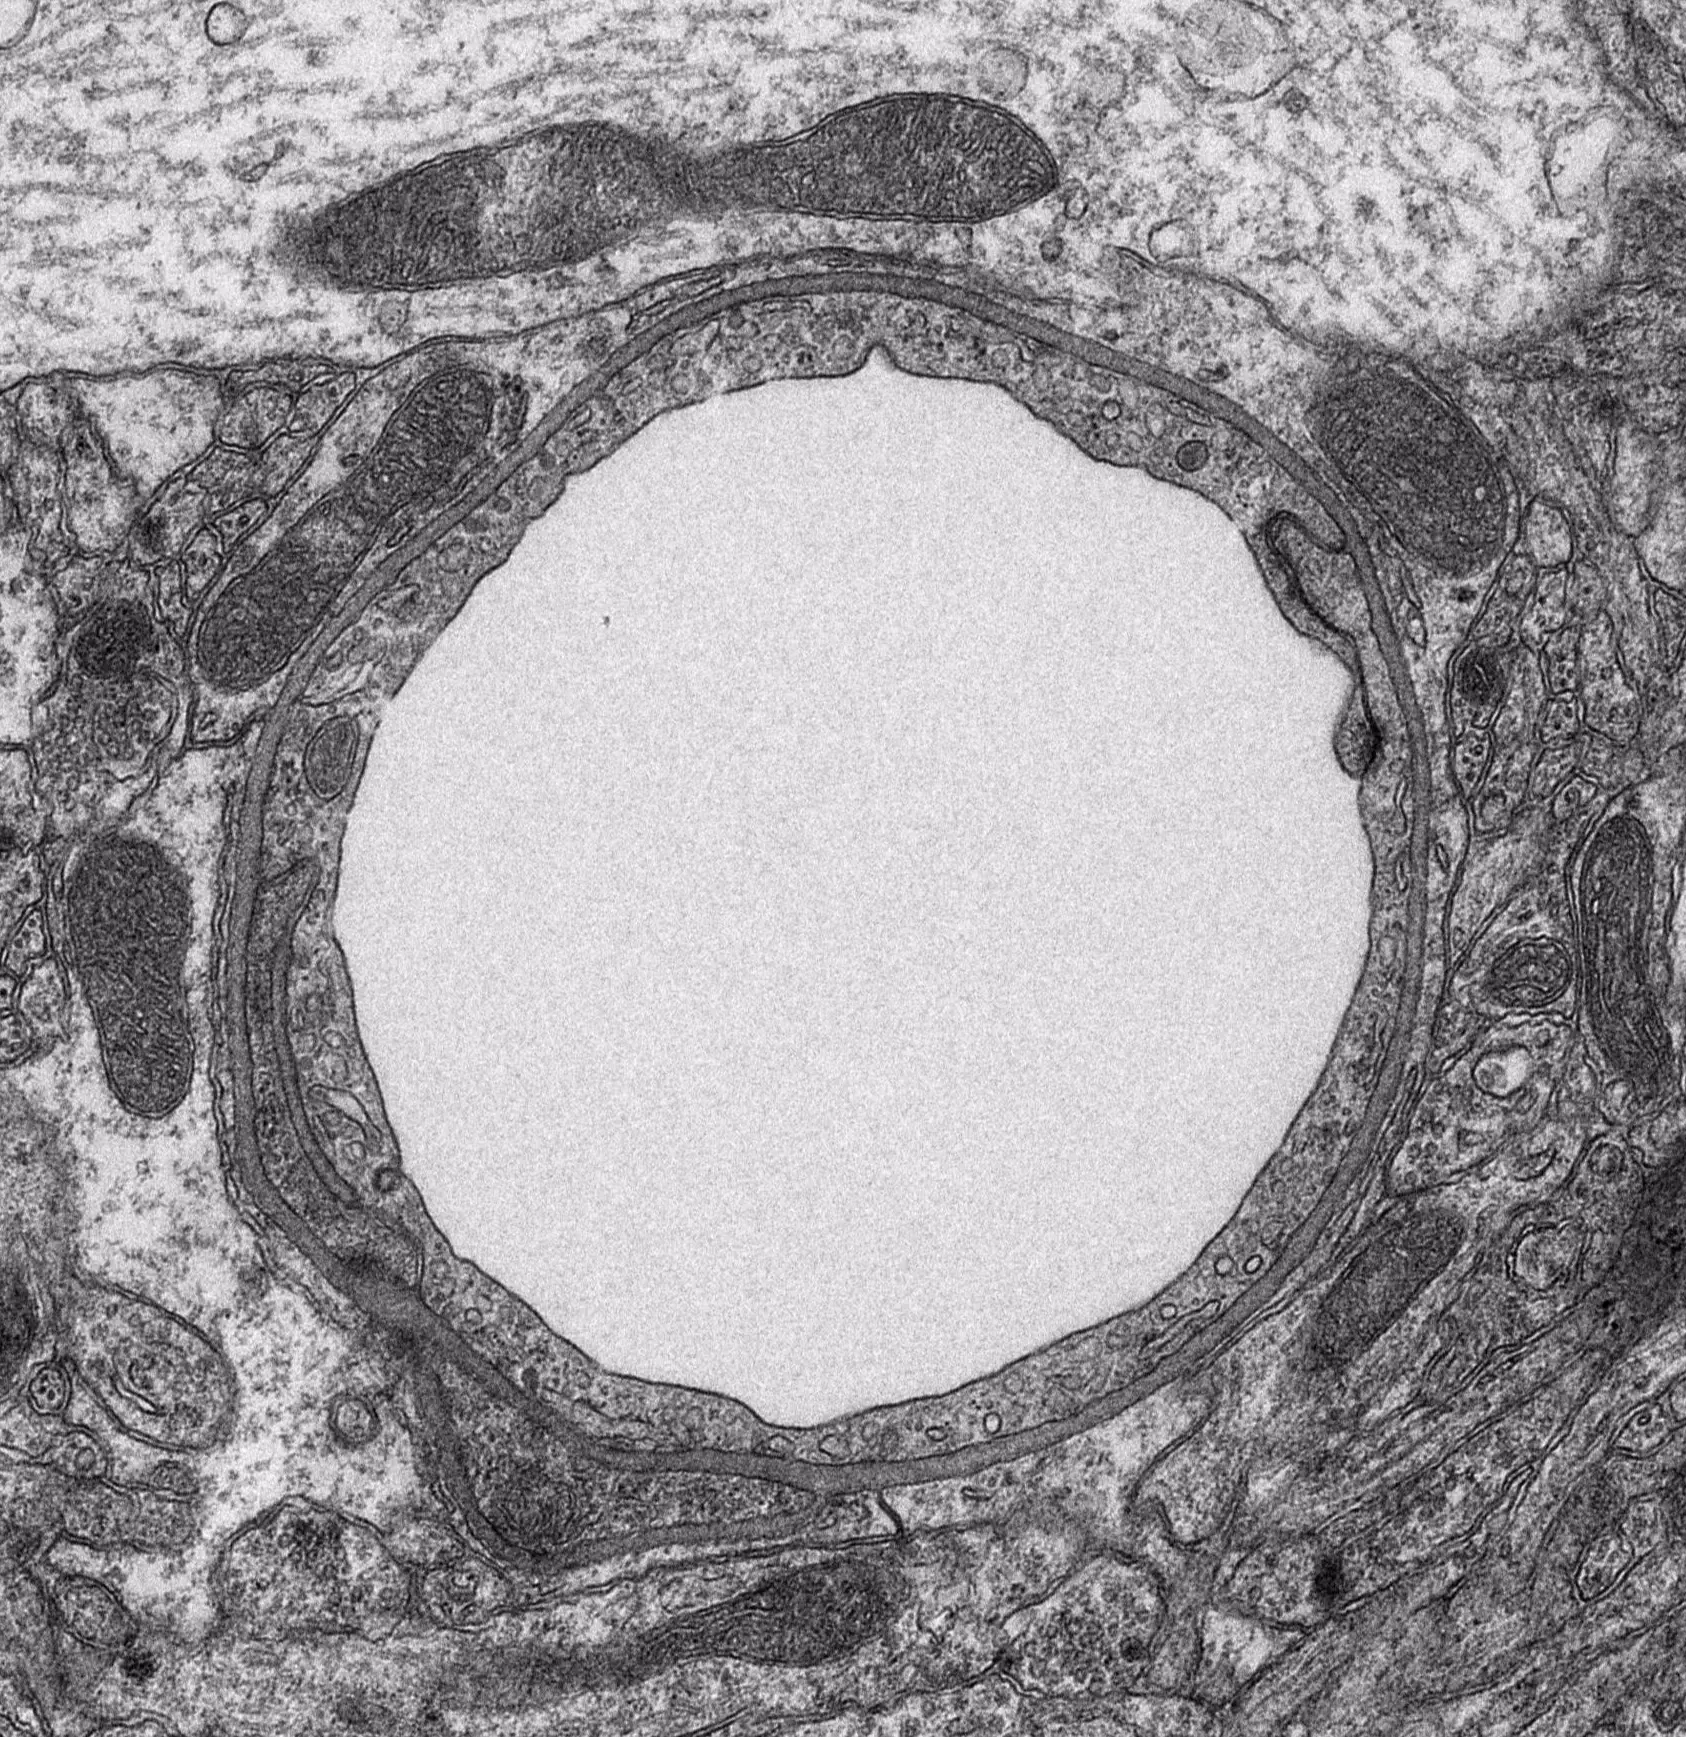

The Wnt pathway was shown by us and others to provide a major signaling cue for vascular barrier formation in the brain. The adherens junction (AJ) protein β-catenin is known to play a crucial role in „canonical“ Wnt signaling, in which activation of frizzled receptors by Wnt-growth factors stabilizes β-catenin in the cytoplasm, leading to its translocation to the nucleus and to target gene transcription via a bipartite transcription factor formed by β-catenin and lomphoid enhancer factor (Lef) / T-cell factor (TCF) (see Scheme 1).

In particular, the role of endothelial Wnt signaling for physiological vessel function and for establishment of vascular hetrogeneity within the CNS is subject of our research. Herein we are focussing on the circumventricular organs (CVOs) that are considered as communication sites between the CNS and the periphery, being invovled in major function such as regulation of thirst fluid homeostasis. Another important aspect of our interest is the identification and validation of endothelial specific Wnt target genes in the BBB. The dual role of β-catenin as a scaffolding protein on the one hand and as a transcription factor on the other makes it an interesting and challenging protein to be studied during vascular development and pathological angiogenesis, like in stroke or malignant brain tumors. Furthermore, we want to shed some light on the role of the Wnt pathway in the formation and/or progression of epileptic seizures. In particular, we are interested in this respect in the crosstalk of Wnt/β-catenin with other pathways and inflammatory reactions.

To study β-catenin and Wnt signaling in the vascular endothelium of the CNS, transgenic mouse lines (reporter and knock-out systems), mouse models of CNS diseases and in vitro culture of primary endothelial cells - also in co-culture with other cell types of the neuro-vascular unit - are employed.